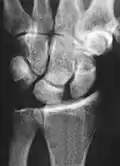

Dynamic scapholunate instability visible upon clenching the wrist -

Scapholunate ligament disruption associated with a Colles' fracture